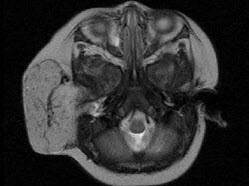

- 单项选择题老年患者,右侧面部肿胀,呈青紫色,MRI检查如图所示,请选择最可能的诊断()。

A、血管瘤

B、囊肿

C、脓肿

D、神经纤维瘤

E、神经鞘瘤

- A